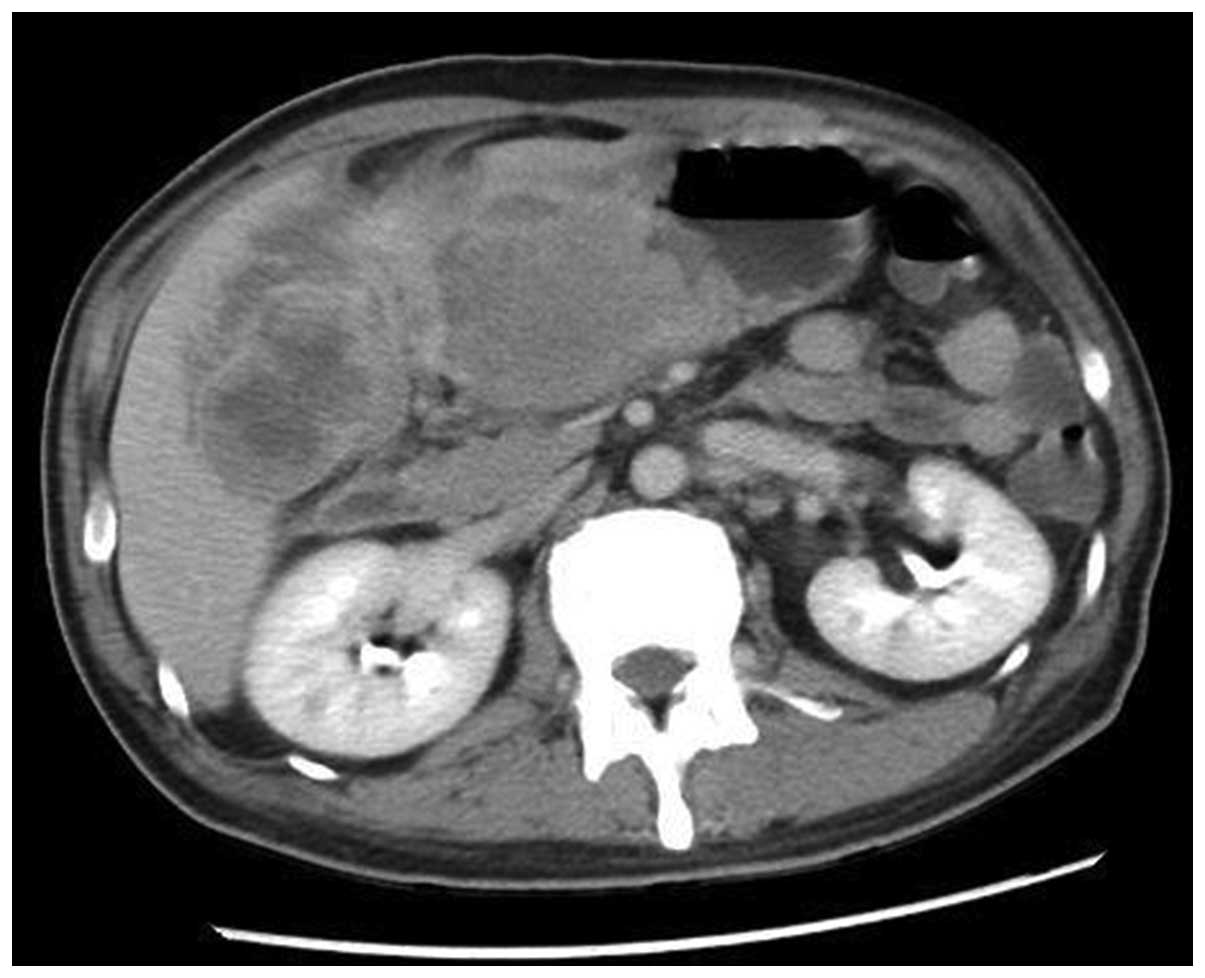

A 49-year-old Chinese male with melena, anemia and fatigue visited the Emergency Room at Ren Ji Hospital Affiliated to Shanghai Jiao Tong University School of Medicine (Shanghai, China), on July 22, 2013. The proband's hemoglobin was 39 g/l upon entering the ward. Abdominal ultrasonography revealed a mass with mixed echogenicity in the right upper quadrant of the abdomen. A computed tomography (CT) scan revealed a 14 cm-diameter mass in the gastric antrum and gastric body, which infiltrated the serosa of the stomach. The gallbladder and hepatic flexure of the colon were also involved. CT contrast enhancement was evident in the two lesions (Figs. 1 and 2). A positron emission tomography (PET)-CT scan revealed a large irregular mass with abnormally high fluorodeoxyglucose (FDG) metabolism in the region of the distal stomach, gallbladder fossa and hepatic tissue in the vicinity (Fig. 3). A lymph node with high FDG metabolism was observed in the region of the pancreatic head (Fig. 4). Endoscopic investigation of the upper gastrointestinal tract identified an irregularly shaped lesion on the gastric antrum and body (Fig. 5). The histopathological section of the endoscopic biopsy revealed that the majority of the tumor cells were spindle shaped in morphology. Following a primary diagnosis of gastric malignancy, the patient received surgery on August 3, 2013. A 14×13×8 cm, solid mass with an irregular surface was identified during surgery. In addition, the No. 13 lymph nodes were markedly enlarged and fused, measuring 20×35 mm. The distal stomach, gallbladder and right hemicolon were resected in order to completely remove the tumor. In addition, an extended D2 lymphadenectomy was also performed. Reconstruction was conducted with the gastrojejunum Roux-en-Y anastomosis (7). Histopathological diagnosis was as follows: Sarcomatoid carcinoma of the gastric antrum and body (14×13×8 cm in size, with serosa invasion), the gallbladder and adjacent colon wall were also involved and No. 13 lymph node metastasis was observed.